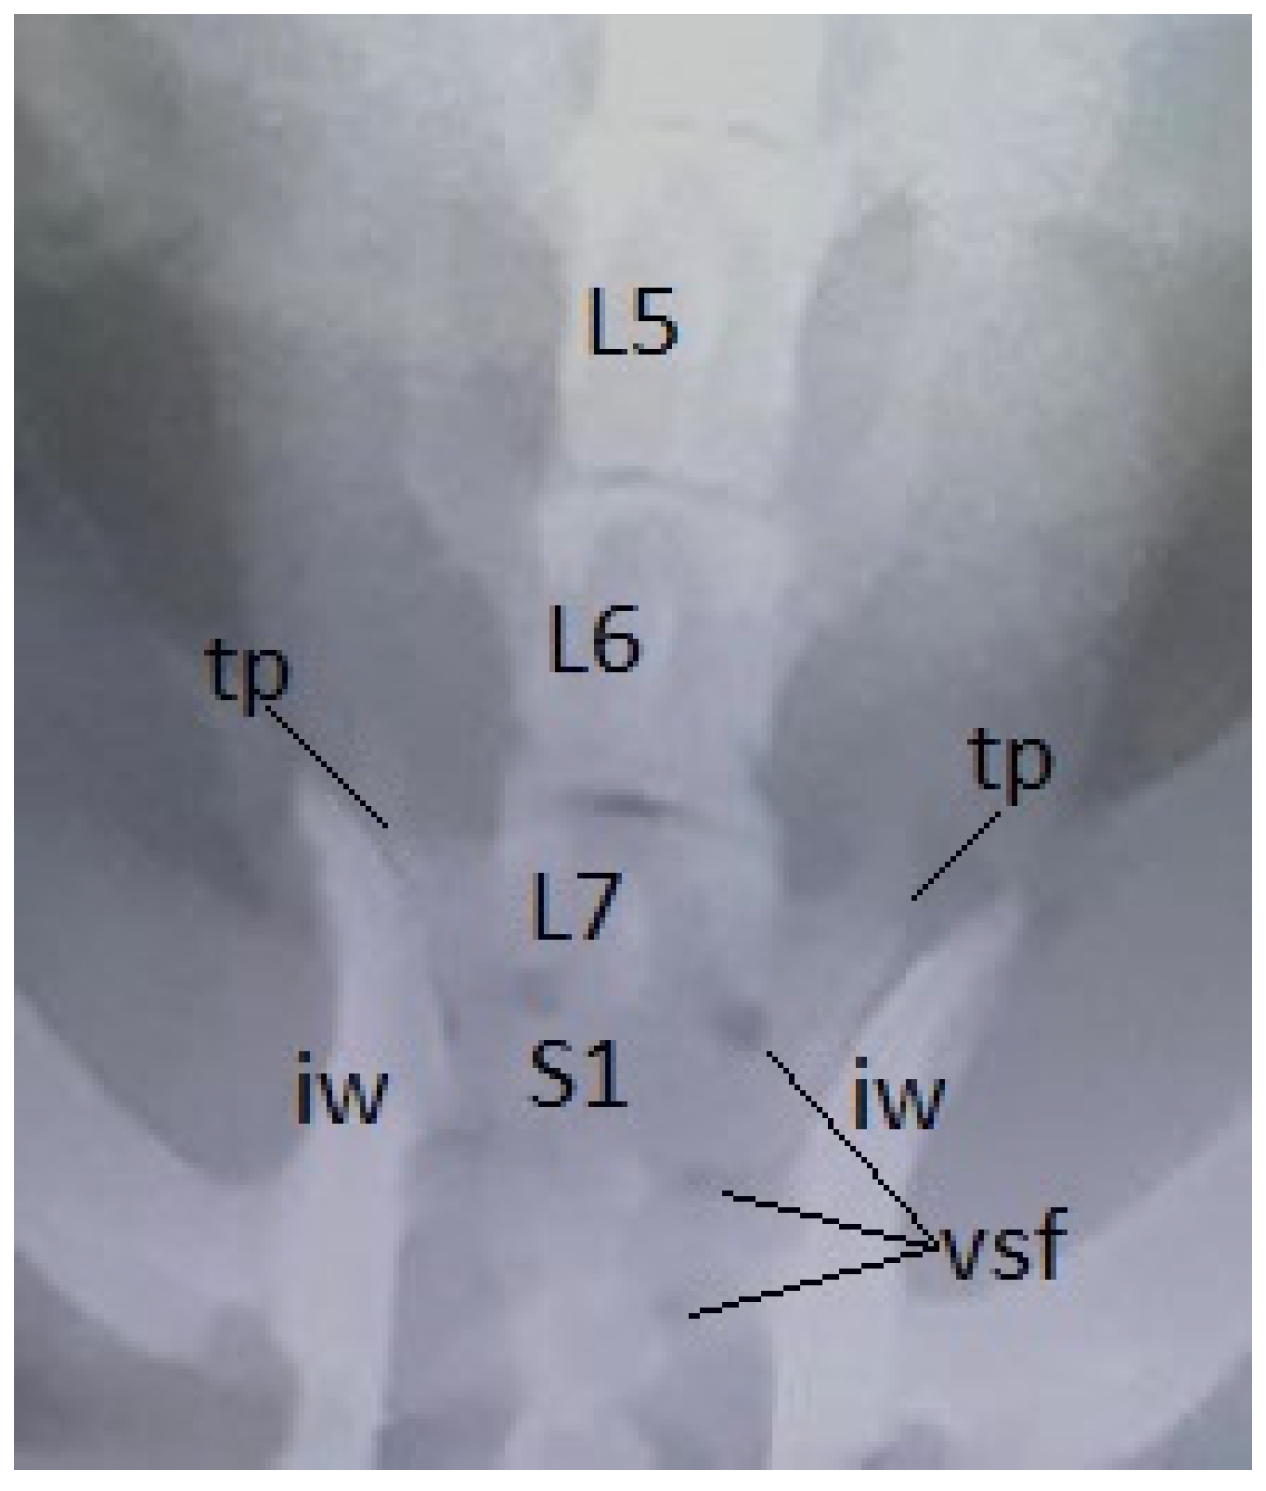

In dogs, among various pathologies, radiologically we identified transitional vertebrae in the lumbosacral junction, having the specific conformation of a lumbar vertebra (supernumerary vertebra) or fused more or less with the sacrum (sacralisation). Three animals had 8 lumbar vertebrae, the last one (L8) being generally shorter (Figure 11, Figure 12), two of them presenting also the sacralisation of L8. In the other dog has been observed the sacralisation of the 7th lumbar vertebra. In all cases the sacralisation was partial and asymmetric, a transverse process having a more appropriate shape to that of a normal one, the other being fused with the sacral wing and taking contact with the iliac wing (Figure 12).

Figure 12. Common breed dog, female, 14 years – supernumerary and asymmetric transitional lumbosacral vertebra (L8), ventro-dorsal view: shortening and sacralisation of L8; L1-L7 – lumbar vertebrae 1-7; the right transvers process (tp) of L8 is thin and not in contact with the iliac wing (iw), but the left one is fused with that of first sacral vertebra (S1) and takes contact with the iliac wing (arrow).

Preprints 91911 g012